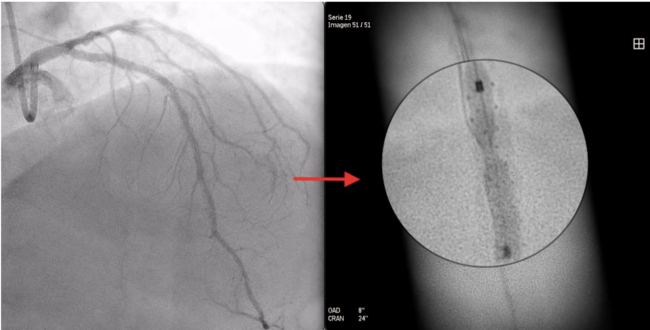

A 73-year-old man was hospitalized with acute coronary syndrome. Angiography showed severely calcified disease in the anterior descending artery and severe stenosis in the proximal, medial, and distal segments (Figure 1). Angioplasty was performed with an NC Trek Neo balloon (Abbott) with proper preparation of the plaque in the proximal and medial segments. Optical coherence tomography showed calcified plaque with a 360° ring and 1.2-mm thickness in the distal segment (Figure 2). Expansion attempts using a super high-pressure 2.5 x 10-mm OPN NC percutaneous transluminal coronary angioplasty (PTCA) balloon (SIS Medical) failed to fracture the calcification; rotational atherectomy with a Rotablator (Boston Scientific) was also unsuccessful. A 1.4-mm excimer laser coronary atherectomy catheter (Spectranetics) was also used (Figure 3) without fracturing the calcification, even after attempts with a super high-pressure balloon at 45 to 50 atm and being inflated for 40 to 60 seconds (Figure 4). Finally, a 3 x 28-mm Angiolite sirolimus-eluting stent (iVascular) was deployed in the proximal segments, followed by a 2.5 x 35-mm paclitaxel-eluting balloon (Medtronic) in the medial segment.

The distal lesion was treated in a deferred session using the LithiX Hertz Contact intravascular lithotripsy system (HC-IVL) (Elixir Medical) (Figure 5), which features a new intravascular catheter with mechanical contact indicated for fragmentation of newly appearing calcified, stenotic lesions in a coronary artery with moderate to serious calcifications before stent insertion. The LithiX HC-IVL’s unique design incorporates stainless steel hemispheres into a semi-compliant balloon; these hemispheres create different pressure points that help fracture calcified plaque via mechanical contact force.

After progressive dilations, maintaining pressures from 8 to 20 atm with a LithiX HC-IVL 2.5 x 10-mm balloon, dilation was performed with a 2.5 x 10-mm OPN NC PTCA balloon at 35 atm for 30 seconds and fracture of the calcium ring was achieved (Figure 6). The patient was discharged without complications or events during follow-up.